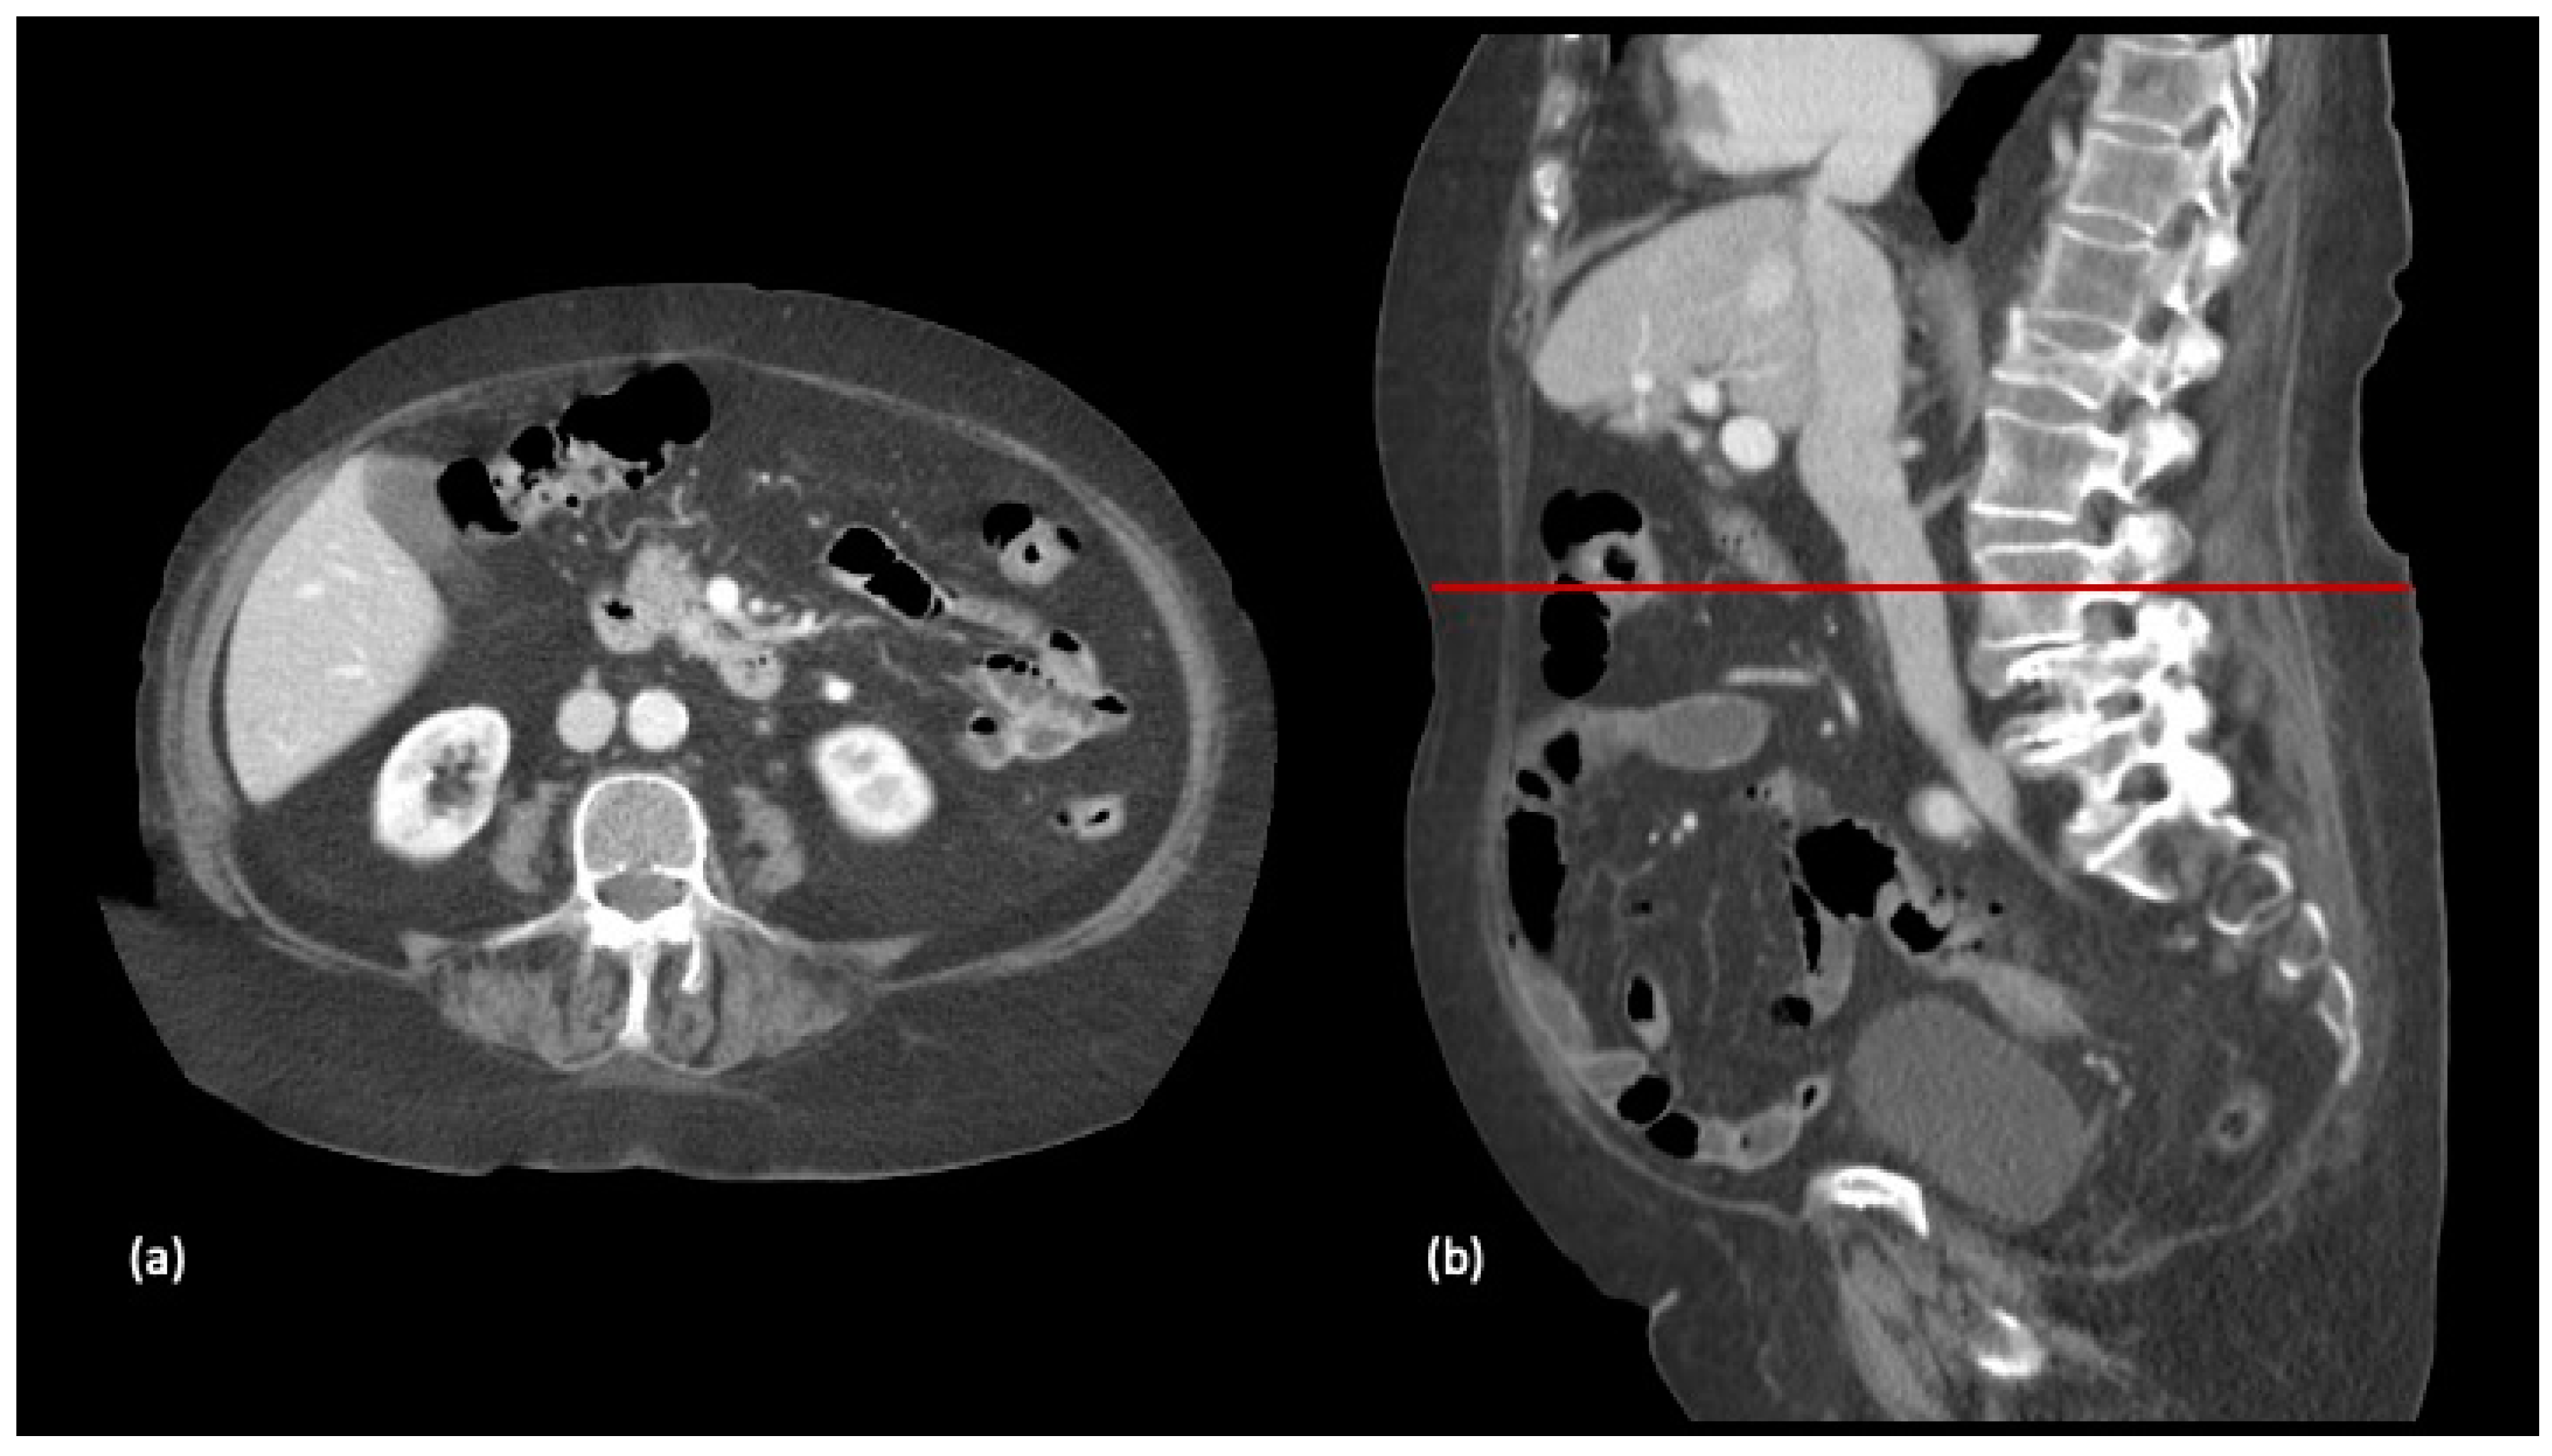

2.4. Body Composition Protocol

- Gomez-Perez, S.; McKeever, L.; Sheean, P. Tutorial: A Step-by-Step Guide (Version 2.0) for Measuring Abdominal Circumference and Skeletal Muscle from a Single Cross-Sectional Computed-Tomography Image Using the National Institutes of Health ImageJ. J. Parenter. Enter. Nutr. 2020, 44, 419–424. [Google Scholar] [CrossRef] [PubMed]